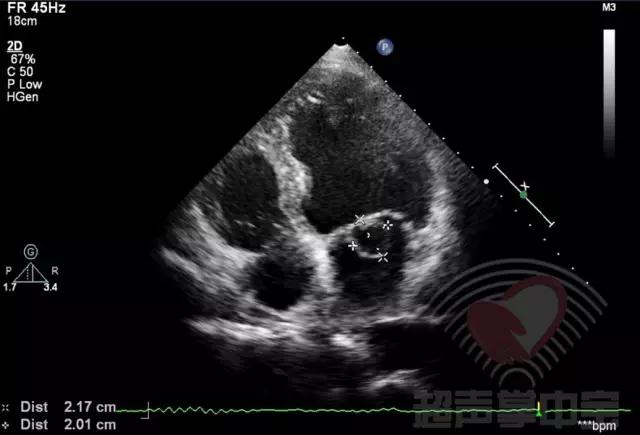

经典病例▏二尖瓣囊肿中竟然全是血液? 图1:心尖四腔心切面显示二尖瓣前叶增厚,前叶左房面可见一囊袋状物附着,大小2.01×2.17cm,囊壁完整,其内透声良好

经典病例▏二尖瓣囊肿中竟然全是血液? 动态图2:四腔心切面显示该囊状物质软,有形变,二尖瓣开放正常